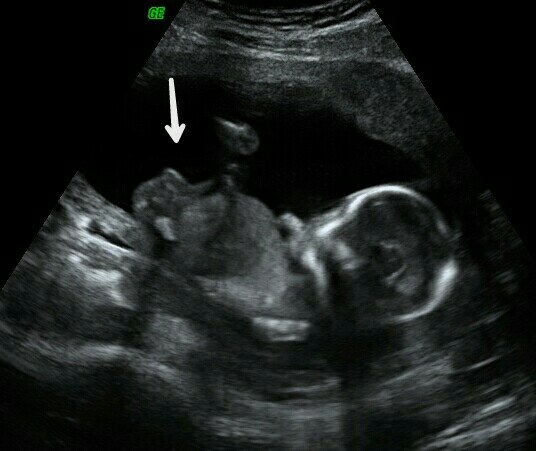

Scan was from 16 weeks. I was curious if the arrow was pointing to anything that shows gender or if it is just something else. I know potty shots are best for determining gender, but I was just wondering.Attachment 34607

Thank you! So, is this the nub (clitoris)? I was confused because I thought there was no more nub at 16 weeks. It just looks weird to me.

There is still a nub of sorts at that stage, so it will look similar.